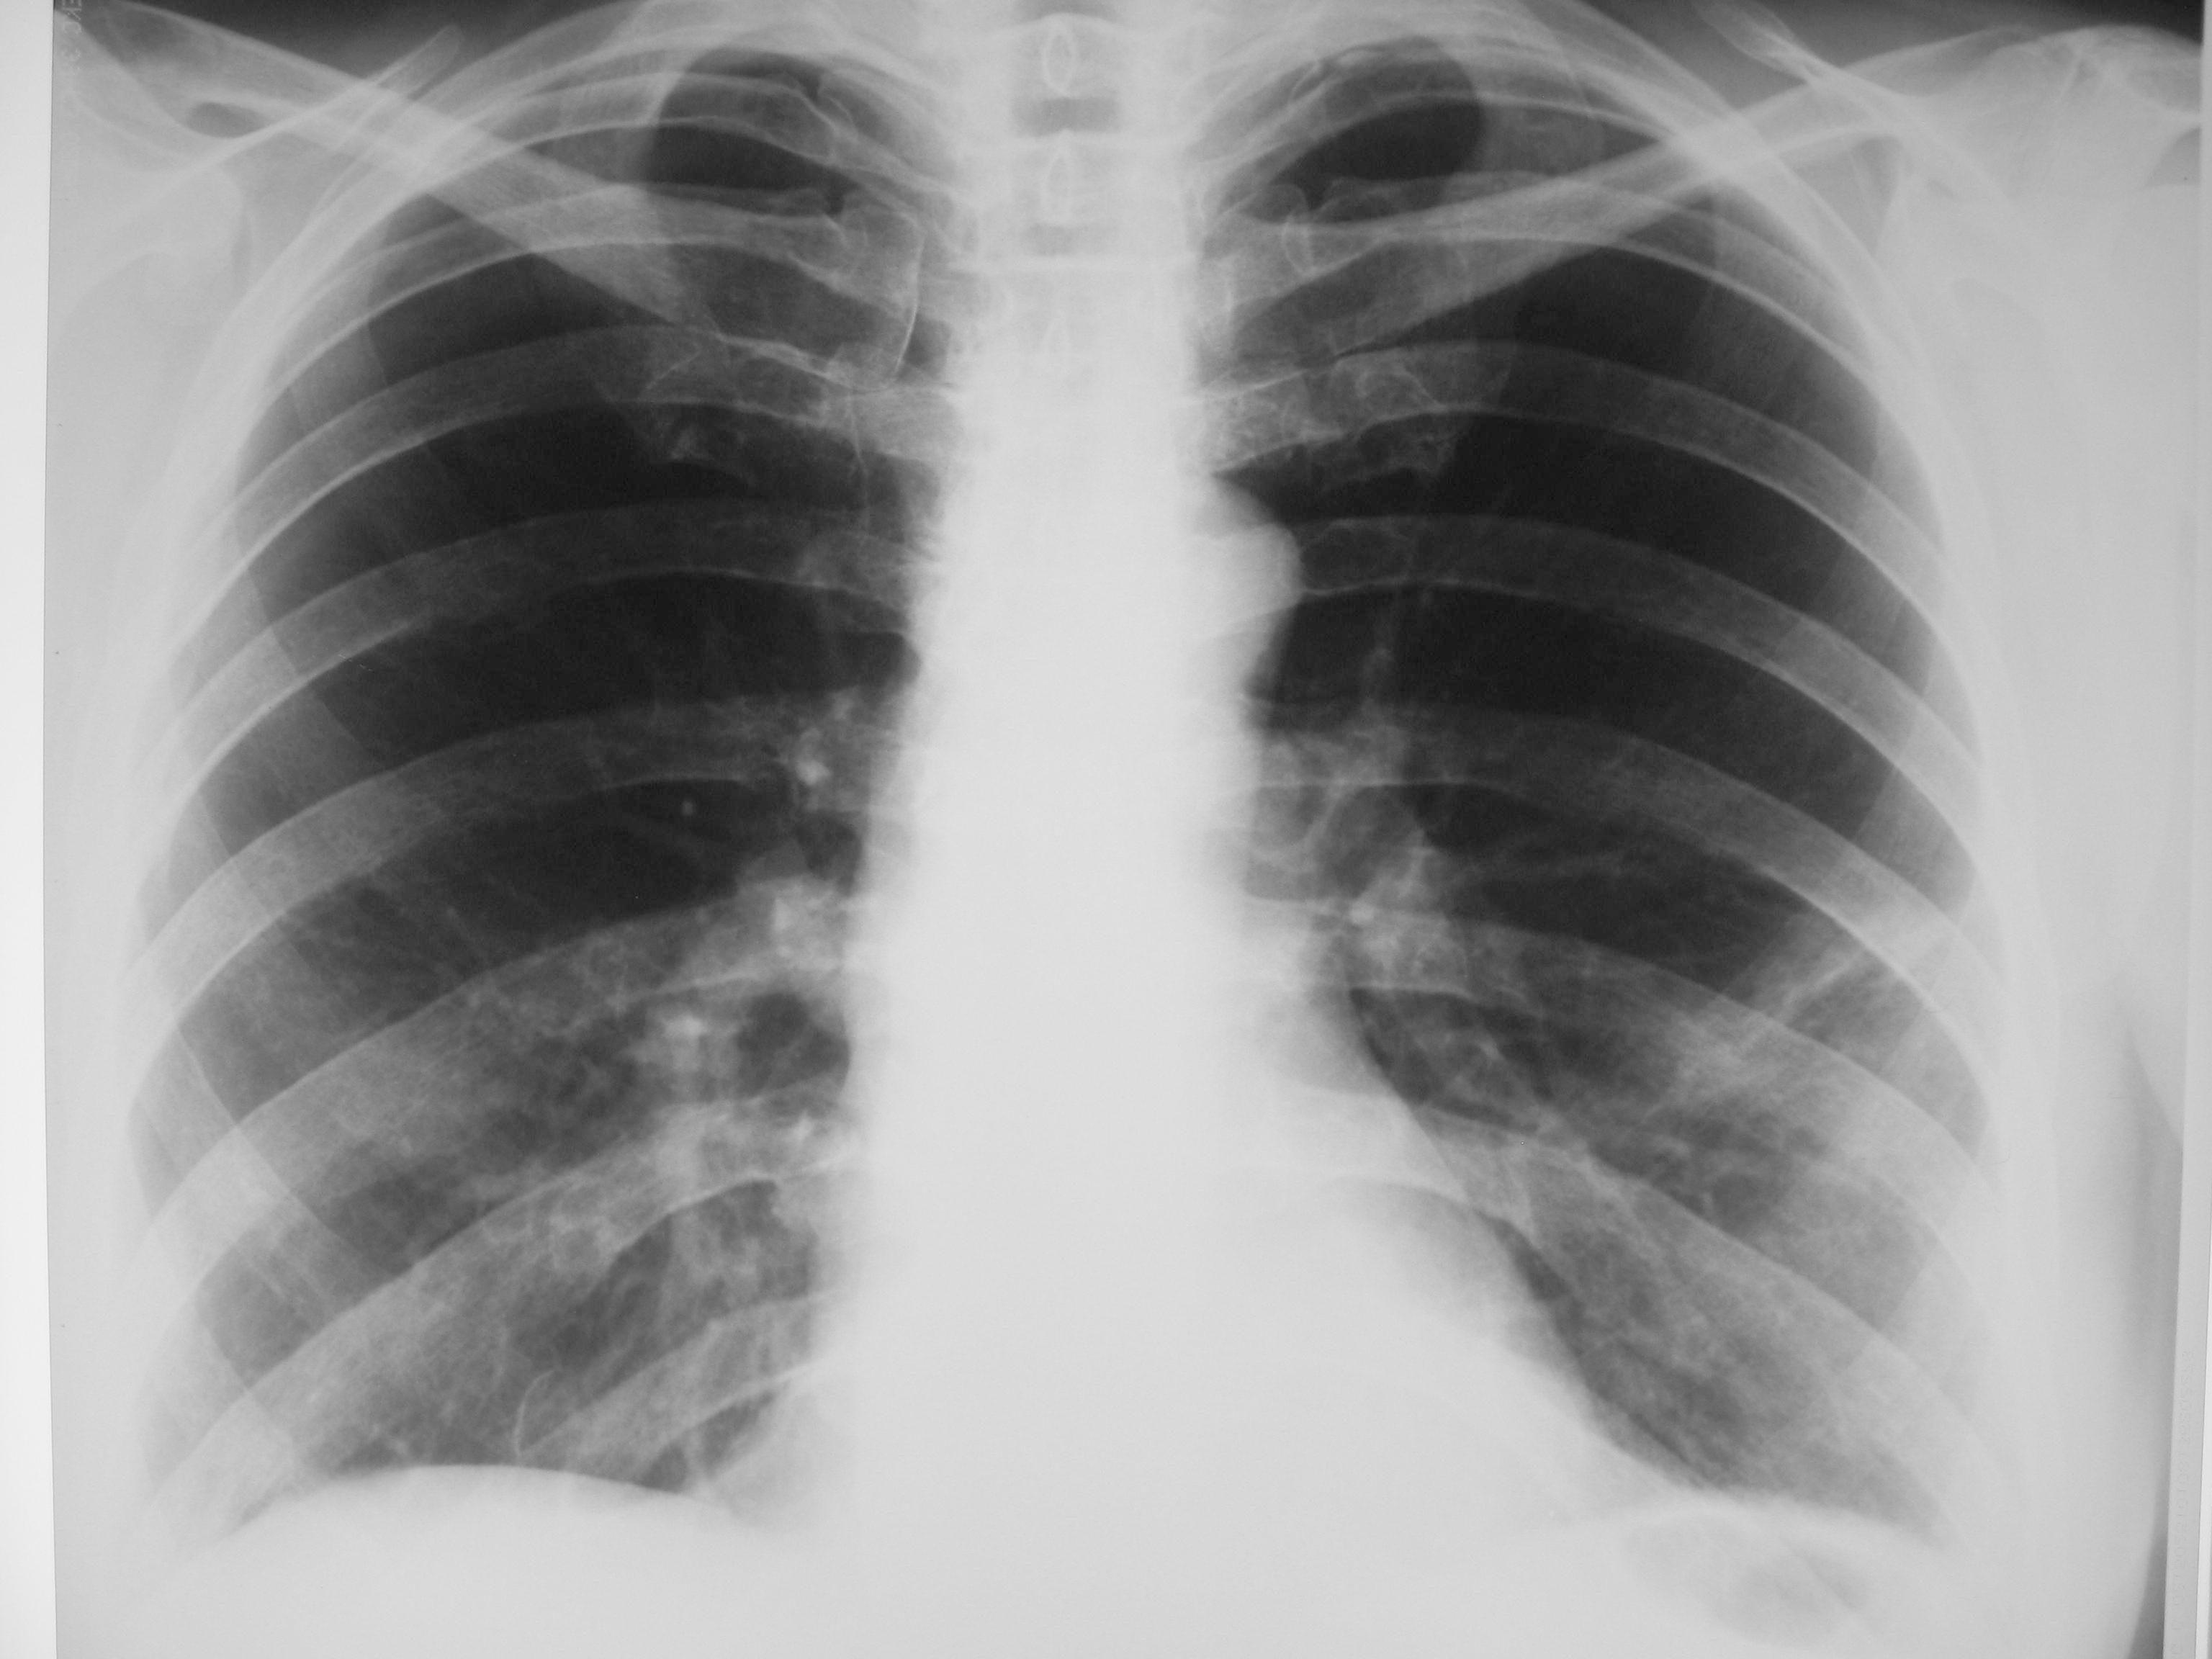

Сегодняшние снимки

img_2738.jpgimg_2739.jpg

Миргалина wrote:

Ну, а Вы боялись. Так есть динамика, а? Так-то, друзья!

Так может начинаться центральный рак. Мало того, изменения могут исчезать на фоне противовоспалительной терапии. А потом появляться вновь.

Дисковидный ателектаз расправился, инфильтрации как не было, так и нет.

Согласна. Была на практике такие случаи, и не раз.Очень боюсь таких пневмоний, часто они параканкрозны. Рентгенконтроль обязателен. После пневмоний рентгенконтроль полагается через 1 месяц ( нас так учили).

Ну так я не спорю. Просто за месяц рентгенологически можем ничего не увидеть, и больного отпускаем,а через 3-наверняка будет, если есть "зло". Практика так показывает, -когда изменения очень малы, как в этом случае. Не настаиваю. Но сделала бы через 3 месяца.или КТ

Так ведь и я не спорю.Если мне не изменяет память, в институте учили ( а это было при царе Горохе), что после пневмонии пациент наблюдается год. Рентгенконтроли проводят через 1,6 и12 месяцев. Можно и флюороконтроль, если флюорограф приличный.Но суть не в этом. Речь идёт о том, что ЭТОГО пациента нельзя оставлять без наблюдения. А кратность контроля определят на месте в зависимости от состояния и самочувствия пациента.